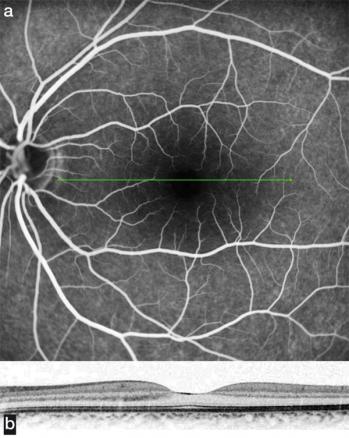

(a) Angiographie à la fluorescéine à l'ophtalmoscope à balayage laser, donnant une grande précision des détails vasculaires, champ de 35°. (b) Coupe optique de la rétine réalisée simultanément par une tomographie en cohérence optique couplée à l'angiographie. Angiographie normale.